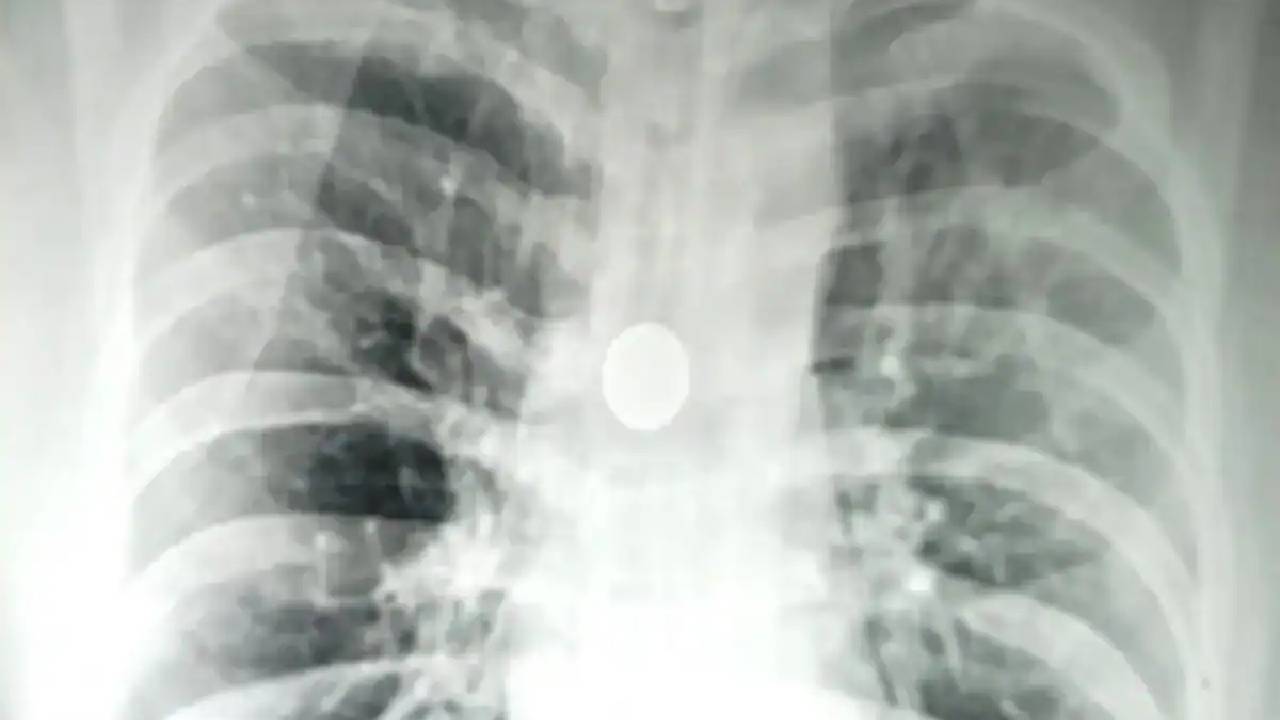

Coin Stuck In Man’s Windpipe: బనారస్ హిందూ యూనివర్సిటీ(బీహెచ్‌యూ)లోని శ్రీ సుందర్‌లాల్ హాస్పిటర్‌లో అరుదైన శస్త్రచికిత్స జరిగింది. 8 ఏళ్లుగా 40 ఏళ్ల వ్యక్తి శ్వాసనాళంలో ఇరుక్కుపోయిన 25 పైసల నాణేన్ని తొలగించారు. కార్డియో-థొరాసిక్ సర్జన్ ప్రొఫెసర్ సిద్ధార్థ్ లఖోటియా మరియు ప్రొఫెసర్ ఎస్‌కె మాథుర్ నేతృత్వంలోని వైద్యుల బృందం మంగళవారం 20 నిమిషాల పాటు ఈ కీలక సర్జరీని చేసి, నాణేన్ని తొలగించారు.

పెద్ద వారిలో దగ్గు అనేది బలంగా ఉండటం వల్ల వస్తువులు శ్వాసనాళంలోకి ప్రవేశించడం చాలా అసాధారణమని, పిల్లల్లోనే ఇలాంటి కేసులు చూస్తామని డాక్టర్ లఖోటియా చెప్పారు. 8 ఏళ్లుగా ఒక బయటి వస్తువు శ్వాసనాళంలో ఉండిపోవడం అనేది చాలా అరుదు అని ఆయన పేర్కొన్నారు. ఇలాంటి సంఘటనలు ప్రాణాపాయం కలిగిస్తాయని, రోగులు ఊపిరి పీల్చుకోవడంలో ఇబ్బందులు, న్యూమోనియా వంటివి ఎదుర్కోవచ్చని, ఊపిరితిత్తలు దెబ్బతినొచ్చని చెప్పారు. మొత్తం సర్జరీ విజయవంతంగా సాగిందని, రోగిని డిశ్చార్జ్ చేశామని వైద్యలు చెప్పారు.

ఇలాంటి శస్త్రచికిత్సలు చేసేటప్పుడు ఖచ్చితత్వం చాలా అవసరమని, ఏ చిన్న లోపం జరిగినా ప్రాణాలకు ప్రమాదమని సర్జరీ కీలక పాత్ర వహించిన డాక్టర్ అమృత రథ్ చెప్పారు. శ్వాసనాళంలోని నాణేన్ని తొలగించేందుకు బ్రోంకోస్కోప్ ఉపయోగించినట్లు చెప్పారు. పెద్దవారిలో ఎవరైనా ఏదైనా వస్తువుని నోట్లో పెట్టుకుని నిద్రించినప్పుడు, మద్యం మత్తులో సెమి కాన్షియస్‌లో ఉంటే శ్వాసనాళంలోకి వస్తువులు చేరే అవకాశం ఉందని చెప్పారు.